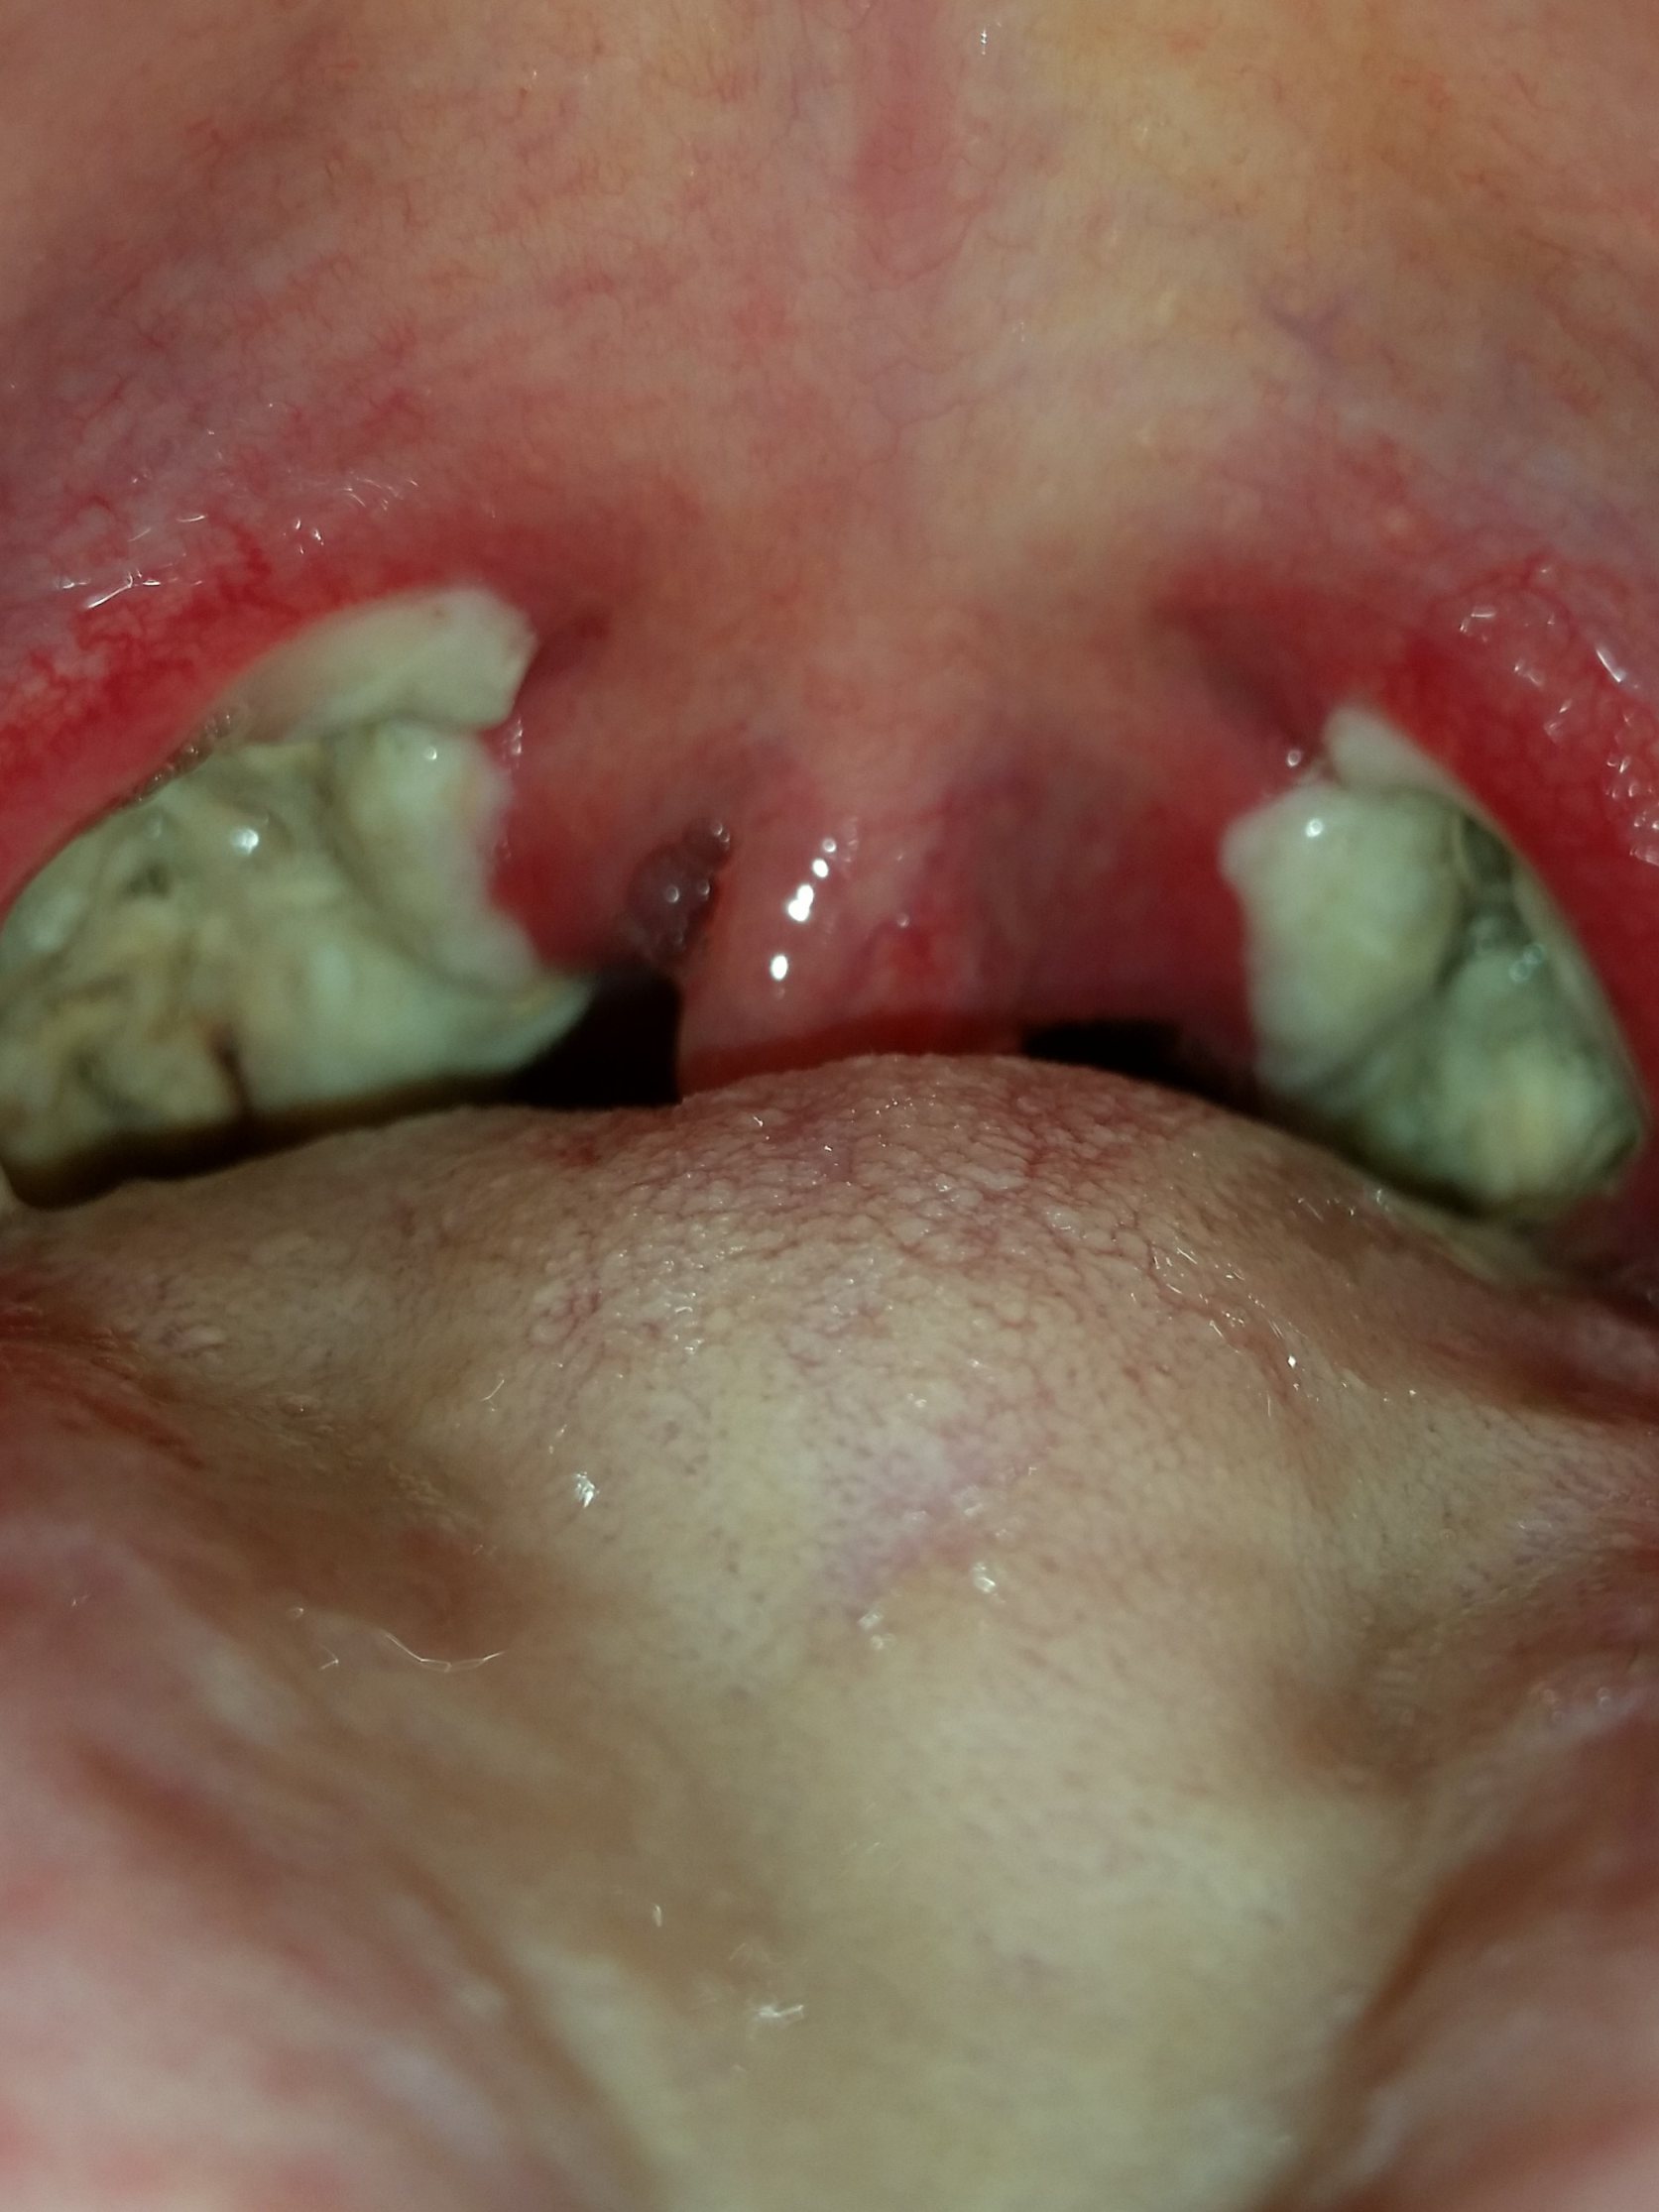

Nach der Operation bildeten sich direkt die weiß, grünlichen Beläge (Fibrinbeläge).

In der ersten Nacht erhielt ich aufgrund meines stark geschwollenen Halszäpfchen eine Cortison Infusion. Schmerzen hatte ich größenteils in der Nacht und am Morgen.

Mandel OP – Bilder Dokumentation Heilungsprozess

- Mandeloperation Tag 0

- Mandeloperation Tag 1

- Mandeloperation Tag 2

- Mandeloperation Tag 3

- Mandeloperation Tag 4

- Mandeloperation Tag 5

- Mandeloperation Tag 6

- Mandeloperation Tag 7

- Mandeloperation Tag 8

- Mandeloperation Tag 9

- Mandeloperation Tag 10

- Mandeloperation Tag 11

- Mandeloperation Tag 12

- Mandeloperation Tag 13